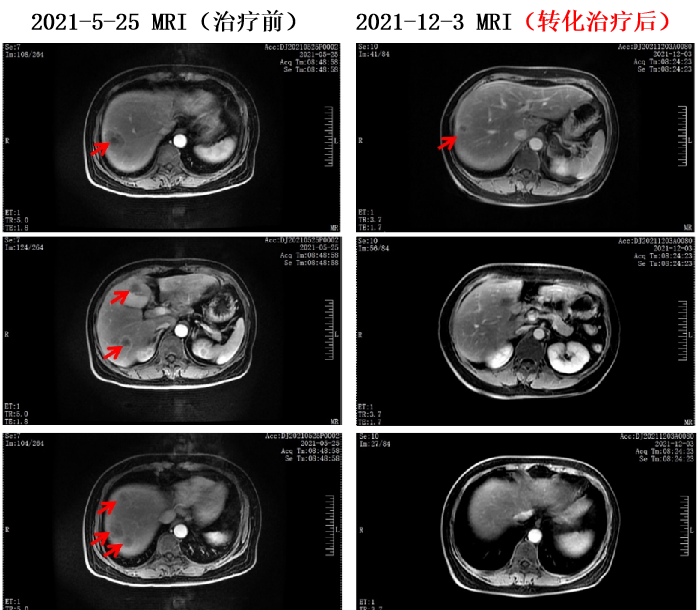

2021-5-29至2021-9-21 共行6周期 贝伐珠单抗+伊立替康+奥沙利铂+卡培他滨方案化疗。

疗效评价为PR,经外科评估可行手术治疗,遂术前停用贝伐珠单抗。

为不降低治疗强度,将卡培他滨调整为雷替曲塞。

2021-10-16至2021-11-9 行2周期 伊立替康+奥沙利铂+雷替曲塞方案化疗。

该病例为晚期结肠癌,经过转化治疗后,病灶明显缓解,获得了手术切除的机会,维持治疗使患者获得了长期的肿瘤控制状态,具有以下特点:

1. 为右半结肠癌,初诊时肿瘤转移广泛,肝内转移,颈部、锁骨上、胸腔、腹腔多发淋巴结转移,表明肿瘤负荷大。

该病例虽然肿瘤负荷大,采用贝伐珠单抗联合三药化疗的方案,显示了原发病灶和肝内转移灶、淋巴结转移灶都获得了明显的控制,部分病灶达到CR,为手术切除创造了良好的机会。因此,对于体力状况好的晚期结直肠癌患者,三药治疗有更好的转化效率;同时,抗血管生成治疗应在更多的晚期结直肠癌病例中推广使用,以使更多的患者能够获得持久的肿瘤缓解。